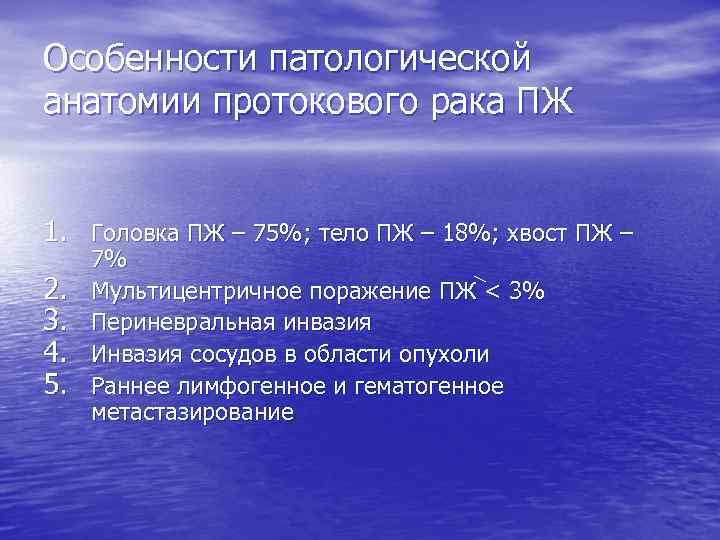

Особенности патологической анатомии протокового рака ПЖ 1. Головка ПЖ – 75%; тело ПЖ – 18%; хвост ПЖ – 2. 3. 4. 5. 7% Мультицентричное поражение ПЖ < 3% Периневральная инвазия Инвазия сосудов в области опухоли Раннее лимфогенное и гематогенное метастазирование